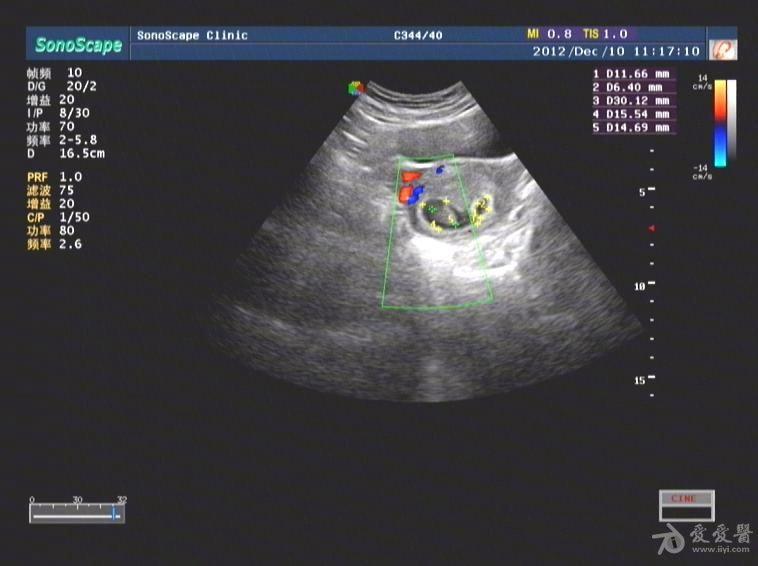

超声孕囊旁积血

超声孕囊旁积血,长孕囊和圆孕囊图片

孕囊周边可见血流信号是什么意思

孕囊旁是什么 超声医学讨论版 爱爱医医学论坛 爱爱医医学网

孕囊周边液性区有积血会自动吸收吗